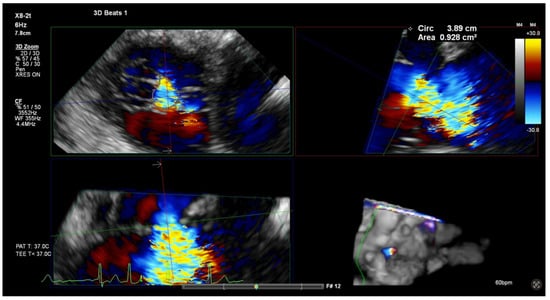

6.2. ICE-Guided TEER